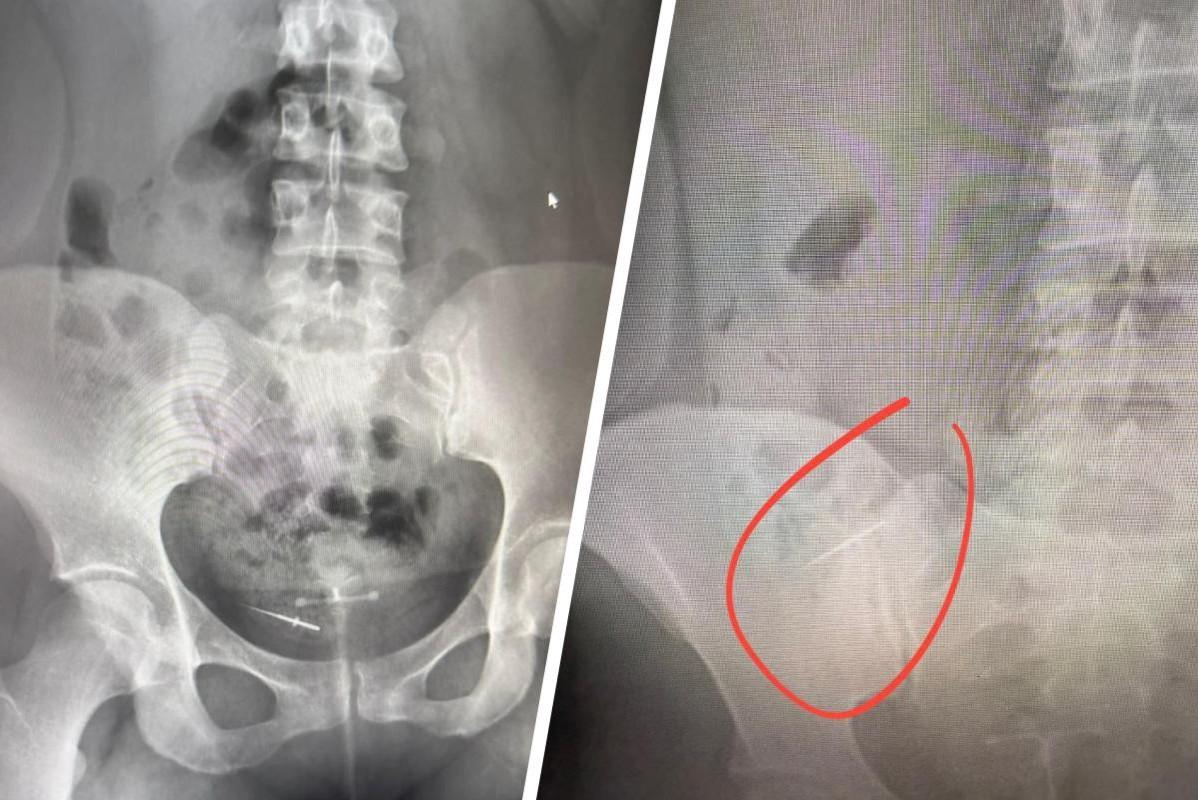

В Башкирии стоматолог забыл во рту пациентки инструмент — ей потребовалась операцияЖенщине пришлось дважды делать УЗИ, чтобы понять причину болей в животе

9 сентября, 2025, 17:25

5 458

26